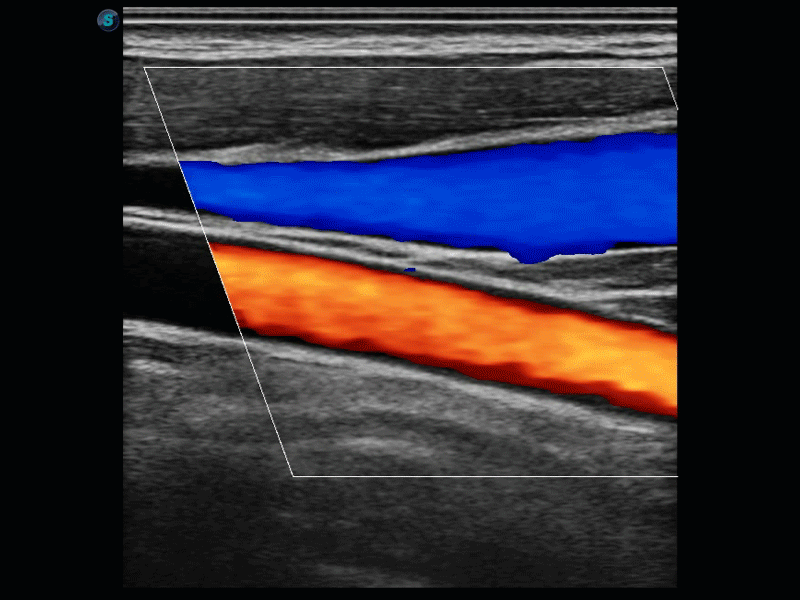

凭借开立医疗先进的成像技术和优异的探头技术提供的清晰的图像表现,您可以更自信地做出临床决策。